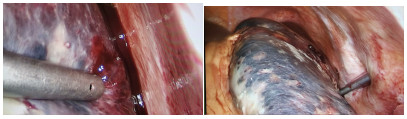

A preliminary study on percutaneous transhepatic drainage combined with sequential percutaneous nephroscopy in treatment of refractory liver abscess

Changhu DUAN, Xiaochen LIU, Jianlong DING, Jianfeng DUAN, Xirong ZHAO, Fan YANG, Ling WU, Lifei ZHAO, Sheng TAI

2021, 37(11): 2622-2625. DOI: 10.3969/j.issn.1001-5256.2021.11.026

Abstract(1082) HTML (221) PDF (2925KB)(64)

Abstract:

Objective  To investigate the clinical effect of percutaneous transhepatic drainage combined with sequential percutaneous nephroscopy for necrosectomy and drainage in the treatment of refractory liver abscess after transcatheter arterial embolization (TACE).  Methods  A retrospective analysis was performed for three patients with refractory liver abscess after TACE in The Affiliated 3201 Hospital of Xi'an Jiaotong University School of Medicine from January 2018 to December 2020, and among the three patients, one had the formation of liver abscess after TACE for hepatic metastases after pancreaticoduodenectomy, one had liver abscess after repeated TACE for massive hepatocellular carcinoma, and one had secondary liver abscess after TACE for traumatic hepatic rupture. All three patients received percutaneous transhepatic drainage and sequential percutaneous nephroscopy for the treatment of refractory liver abscess, and their specific treatment process was summarized.  Results  All three patients were diagnosed with refractory liver abscess based on CT, routine blood test, procalcitonin, blood culture, and clinical manifestation. Percutaneous transhepatic catheterization under the guidance of conventional ultrasonography or CT and effective antibiotics had an unsatisfactory therapeutic effect, and after sequential percutaneous nephroscopy was performed for necrosectomy and drainage, liver abscess was cured and the patients had good prognosis.  Conclusion  For refractory liver abscess after TACE, when routine puncture treatment has an unsatisfactory therapeutic effect or a patient cannot tolerate surgical operation, percutaneous transhepatic drainage combined with sequential percutaneous nephroscopy is safe and effective in the treatment of refractory liver abscess.